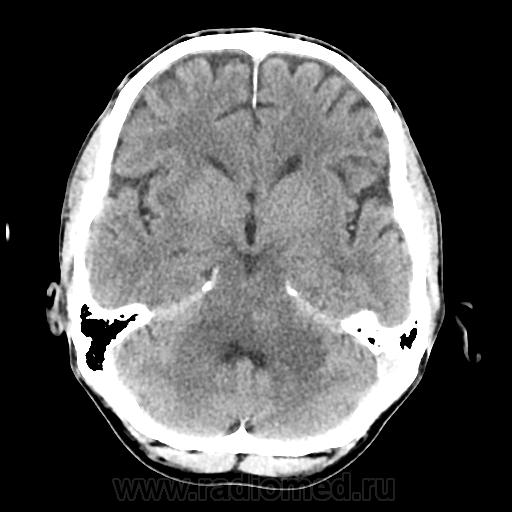

КТ ГМ+C Субтенториальное объемное образование в стволе головного мозга (мост)

Мужчина 46 лет. Поступил с подозрением на ОНМК. Жалобы на шаткую походку, снижение зрения. Мост содержит ядра ЧМН (V, VI, VII, VIII). Для невриномы и менингиомы не  характерна локализация. Узловое, экспансивно растущее образование, интенсивно накапливает КВ. DDs: Кавернозная ангиома, mts.

Ну да, перифокального отека нет, лишь IV желудочек компремирован. МРТ точно рассудит.

Да как то не выражен, может незначительный, IV желудочек не резко  деформирован и сужен.

По-моему отека предостаточно.

мост и левая средняя мозжечковая ножка гипо-, цистерн ЗЧЯ вообще не видно...